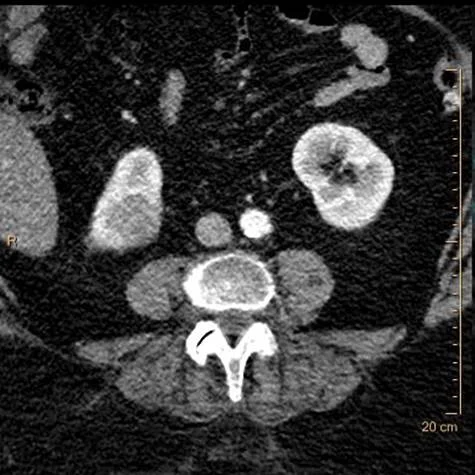

Routine followup CT on a 65 year old female with treated lung cancer. We read a bunch of these, and the interpretation is often “no significant change”, which is good news for the patient. Every exam deserves careful scrutiny, and spectral CT can very often add value in these cases.

Careful look at the kidneys on conventional CT in this case might reveal lesions, but spectral CT makes them really easy to pick up.

Conventional CT: Do you see the lesion in lower pole of the right kidney?